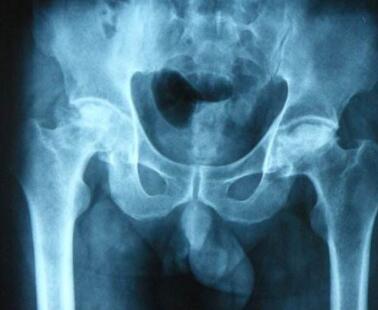

河南股骨头坏死医院介绍股骨头坏死早期症状有哪些?

股骨头坏死早期症状有哪些?股骨头坏死医院怎么样,治疗股骨头坏死专家为您讲解:出现股骨…[详情]

专业治疗股骨头专家介绍双侧股骨头坏死如何治疗?

双侧股骨头坏死如何治疗?河南专业治疗股骨头坏死专家为您降级:对于双侧股骨头坏死,一旦…[详情]

河南骨科医院介绍股骨头坏死早期症状是什么?

股骨头坏死的早期症状有哪些?股骨头坏死医院,骨科医院治疗股骨头坏死专家为您讲解:股骨…[详情]